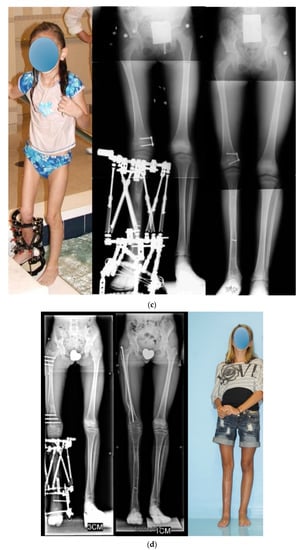

Figure 6.

(a) Preoperative radiographs and photographs of an 18-month-old girl born with Paley type 3a FH. She has fixed equinovalgus of the foot and a procurvatum-valgus diaphyseal tibial deformity. (b) Photograph (left) and radiograph (middle left) after the SUPERankle procedure combined with application of a circular external fixator for 5 cm of lengthening. Radiographs of the lower limbs after removal of the external fixator (right middle and right). (c) Photograph (left) and radiograph (middle) showing second lengthening of tibia at age 8, using computer dependent external fixator. She is shown doing pool therapy. Radiograph after removal of external fixator with correction of distal femoral valgus malalignment by hemiepiphysiodesis (right). (d) Radiograph showing the third and final lengthening of the tibia with lengthening of the femur both with external fixation at age 13. Radiograph after removal of the external fixators showing excellent alignment and equalization of limb lengths (middle). Final photograph at age 16 years after skeletal maturity with equal leg lengths and excellent function.